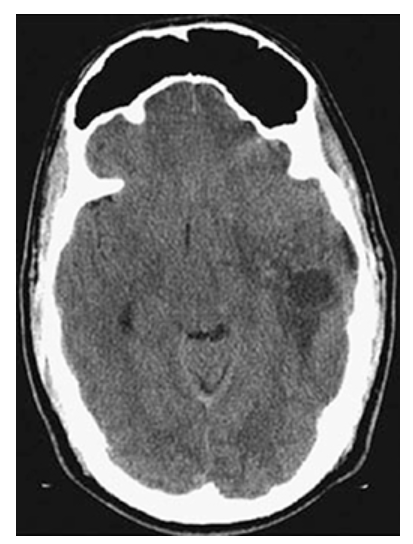

Astrocytoma. Axial NECT of the head shows a low-attenuation mass in the left temporal lobe with surrounding edema.